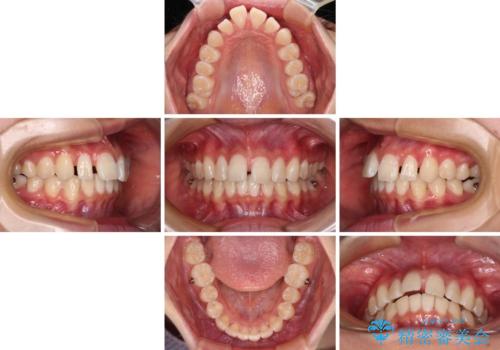

インビザライン単体で対応することも検討できますが、達成する可能性が低いため、カリエールディスタライザーという補助装置を併用して、より確実性を上げることとしました。

奥歯の咬み合わせと深い咬み合わせを改善した後、隙間などをインビザラインで整えることとしました。